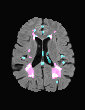

In recent years, data-driven machine learning (ML) methods have revolutionized the computer vision community by providing novel efficient solutions to many unsolved (medical) image analysis problems. However, due to the increasing privacy concerns and data fragmentation on many different sites, existing medical data are not fully utilized, thus limiting the potential of ML. Federated learning (FL) enables multiple parties to collaboratively train a ML model without exchanging local data. However, data heterogeneity (non-IID) among the distributed clients is yet a challenge. To this end, we propose a novel federated method, denoted Federated Disentanglement (FedDis), to disentangle the parameter space into shape and appearance, and only share the shape parameter with the clients. FedDis is based on the assumption that the anatomical structure in brain MRI images is similar across multiple institutions, and sharing the shape knowledge would be beneficial in anomaly detection. In this paper, we leverage healthy brain scans of 623 subjects from multiple sites with real data (OASIS, ADNI) in a privacy-preserving fashion to learn a model of normal anatomy, that allows to segment abnormal structures. We demonstrate a superior performance of FedDis on real pathological databases containing 109 subjects; two publicly available MS Lesions (MSLUB, MSISBI), and an in-house database with MS and Glioblastoma (MSI and GBI). FedDis achieved an average dice performance of 0.38, outperforming the state-of-the-art (SOTA) auto-encoder by 42% and the SOTA federated method by 11%. Further, we illustrate that FedDis learns a shape embedding that is orthogonal to the appearance and consistent under different intensity augmentations.